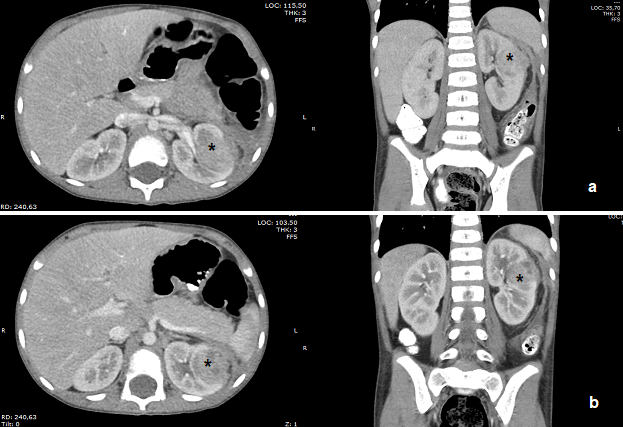

Nefronía lobar aguda en el paciente pediátrico. Reporte de caso

Viviana Barragan Arévalo, Juliana Mancera Morales, Viviana Echeverri Restrepo, Jesús Niño Salcedo, Juan Pablo Luengas Monroy

3-6